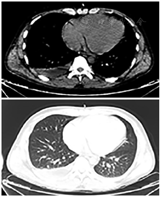

心脏扩大,双侧胸腔积液

患者男性,32岁,因"双下肢水肿半月"入院。患者自述于2022年5月5日因双下肢水肿自服呋噻米治疗,双下肢水肿逐渐好转。2022年5月10日出现胸闷、呼吸困难等,且症状持续加重,2 d后出现低血压、少尿(约200 ml/d)等表现。当地医院给予抗感染及血管活性药物等治疗,但症状持续加重,于2022年5月13日转入武汉大学中南医院治疗。既往体健,无高血压病、糖尿病、心肌炎等病史,无酗酒及毒品接触史等,平常喜欢进食烧烤食物,偶饮啤酒。体检:体温36.5℃,脉搏111次/min,呼吸43次/min,血压81/40 mmHg(去甲肾上腺素剂量1 μg·kg-1·min-1),体质指数28.1 kg/m2;烦躁,皮肤潮湿、四肢湿冷,皮肤、巩膜黄染,端坐呼吸,双肺呼吸音清,心率111次/min,律齐,未闻及明显病理性杂音,腹软,肝脾未触及,双下肢无水肿,四肢肌力检查不配合,病理反射阴性。辅助检查(表1):血气分析显示PH值、二氧化碳分压(PCO2)及碳酸氢盐降低,乳酸明显升高,提示代谢性酸中毒并呼吸性碱中毒,因患者乳酸升高明显,考虑乳酸酸中毒。血常规及生化指标等检验结果显示白细胞、肌酐、尿素氮、谷丙转氨酶、谷草转氨酶、总胆红素、直接胆红素、B型利钠肽、降钙素原等均升高,尿常规显示尿白细胞及尿蛋白均为阴性。胸腹部CT检查提示:心脏扩大、双侧胸腔积液(图1);脂肪肝。超声心动图显示:左心房3.8 cm (参考值:2.2~3.5 cm)、左心室舒张末期内径5.4 cm(参考值:3.6~5.3 cm)、右心房内径5.1 cm(参考值:2.2~4.4 cm)、右心室舒张末期内径5.1 cm(参考值:2.0~4.2 cm)、左室射血分数62%(参考值:50%~75%),提示全心扩大。脉搏指示连续心排血量监测(PiCCO)(表2)显示心排血量、心脏指数及中心静脉压均升高,而外周循环阻力降低;中心静脉血气分析(表2)显示中心静脉血氧饱和度明显升高,结合患者近2个月长期进食烧烤食物的特点。诊断:(1)分布性休克:"Shoshin脚气病"?感染性休克?(2)中毒?(3)多器官功能衰竭(循环衰竭、肝功能衰竭、肾功能衰竭)。患者的胃液、尿液及血液标本被送至湖北省毒物检测中心检测,均未发现中毒证据;血液及肺泡灌洗液样本病原微生物宏基因(NGS)测序未发现细菌、真菌及病毒感染,血及肺泡灌洗液样本细菌学培养结果也均为阴性,胸腹部CT检查未提示感染,排除脓毒症所致的感染性休克。患者给予维生素B1注射液100 mg(3次/d)肌注治疗,维生素B1治疗3 h后,患者的血流动力学逐步稳定,去甲肾上腺素使用剂量开始逐渐减少,3 d后停用了去甲肾上腺素(图2)。呼吸困难等逐渐好转,血清乳酸水平快速下降,肝、肾功能及B型利钠肽等逐渐恢复正常(表1)。维生素B1治疗2 d后查血清维生素B1为46.547 nmol/L(参考值:50~150 nmol/L),提示硫铵素缺乏。患者经维生素B1肌注治疗1周后,换用了维生素B1片(30 mg/d)口服治疗。患者康复出院,随访期间未发生胸闷、喘气、水肿等表现,复查肝肾功能均正常。